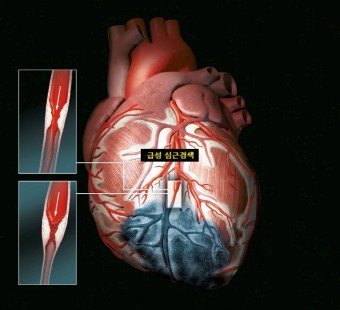

오늘은 정말 많은 분들이 놓치기 쉬운 **치명적인 심장 질환, ‘심근경색’**에 대해 이야기해보려 합니다.심근경색은 말 그대로 심장 근육이 괴사하는 질환으로, 골든타임을 놓치면 생명을 잃을 수 있는 응급상황입니다.

1. 쥐어짜는 듯한 가슴 통증 (흉통)

심근경색의 가장 전형적인 증상입니다.

가슴 중앙 또는 왼쪽 가슴 부근에서 극심한 압박감, 조이는 느낌, 짓누르는 듯한 통증이 나타나며

5분 이상 지속되는 경우가 많습니다. 통증은 휴식으로 사라지지 않고 점점 심해지기도 합니다.